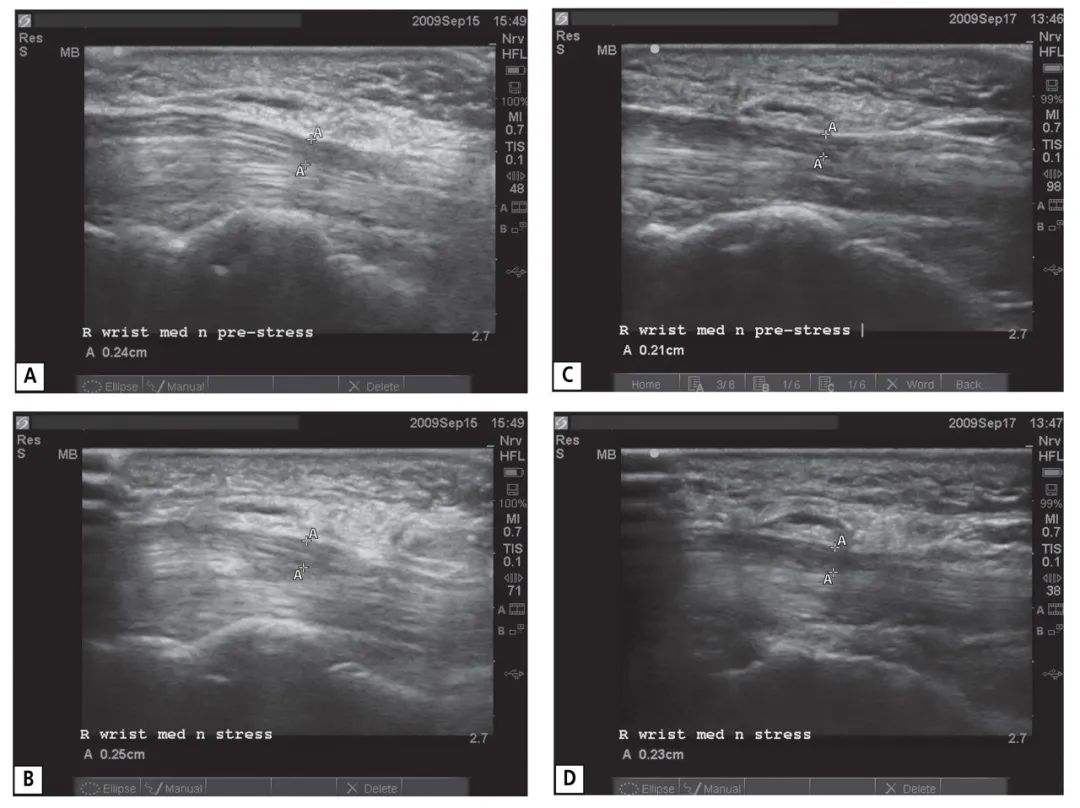

兩個沒有腕管綜合癥的對照對象的右手腕的超聲波圖像。第一個對照對象的正中神經(jīng)在預應力(A)和應力(B)期間的縱向圖像描述了 "A "標記之間的神經(jīng)直徑測量。這些測量結果顯示最初的神經(jīng)直徑為0.24厘米,在壓力下增加到0.25厘米,表明沒有受到壓迫。第二個對照對象的正中神經(jīng)在預應力(C)和應力期間(D)的縱向圖像也描述了 "A "標記之間的神經(jīng)直徑測量。這些測量結果顯示最初的神經(jīng)直徑為0.21厘米,在應力期間增加到0.23厘米,表明沒有受到壓迫。